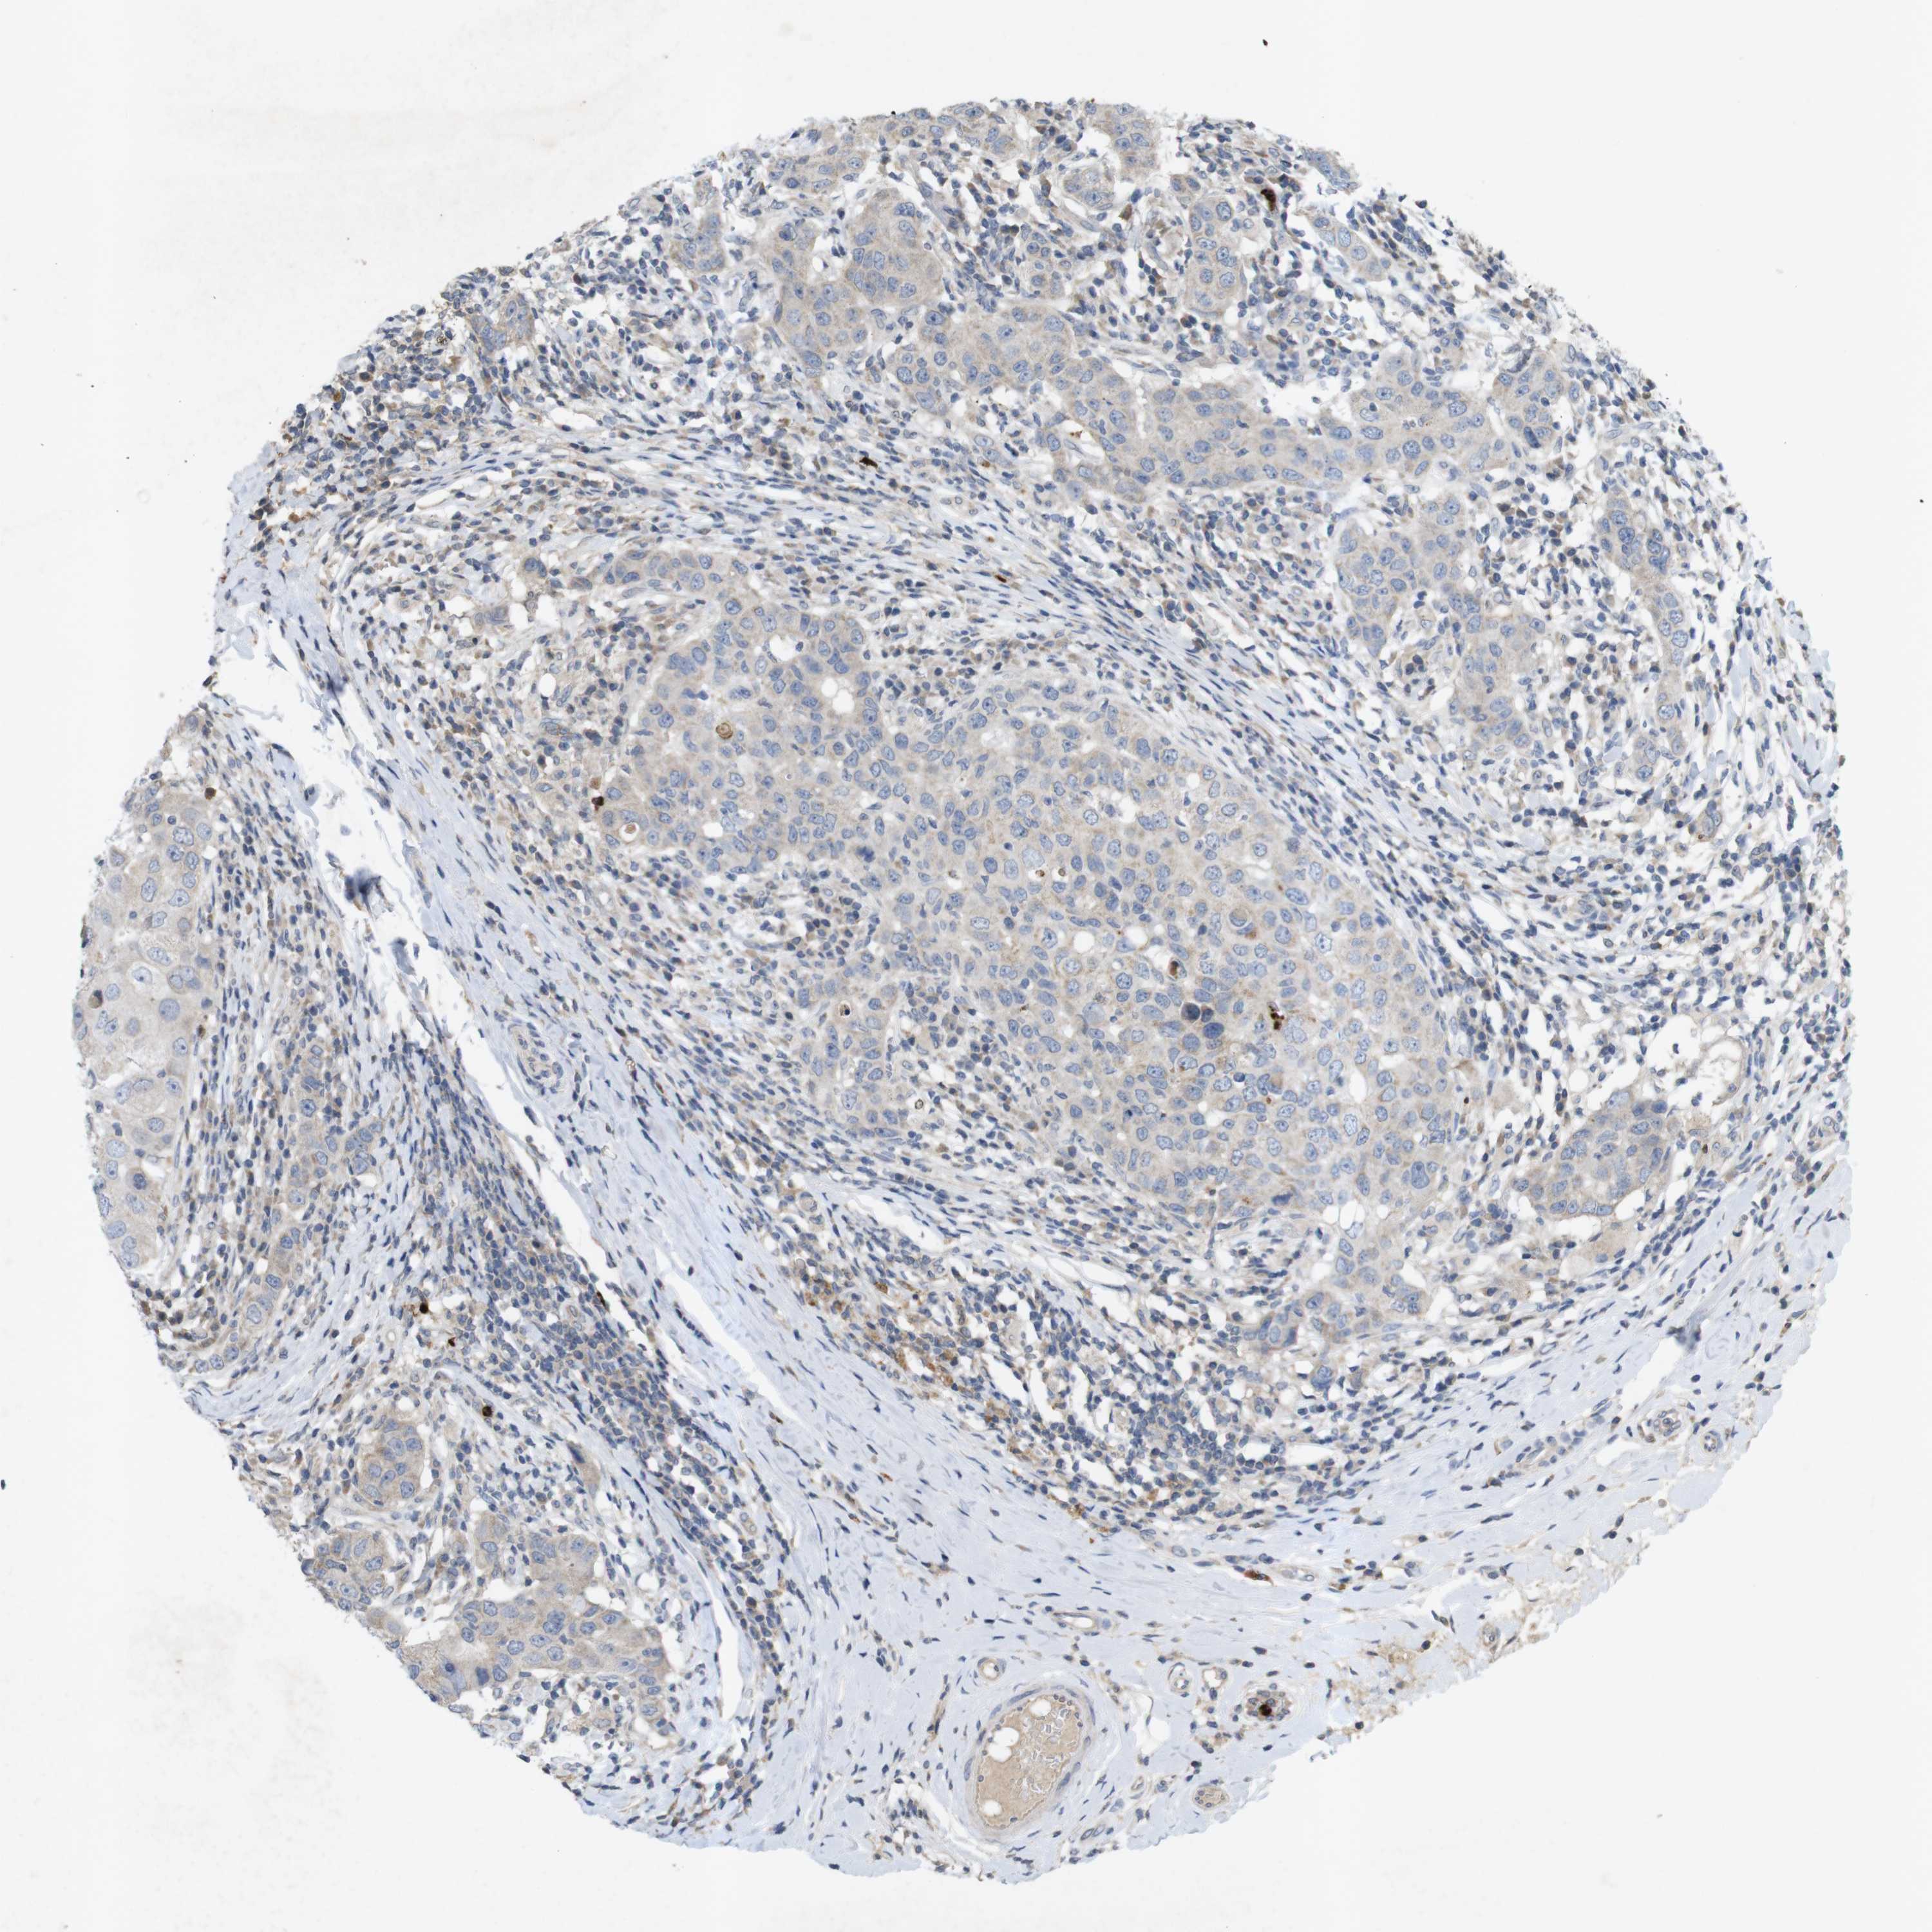

BRCA TCGA BRCA VALIDATION PROTEIN EXPRESSION

ANTIBODIES

AND

VALIDATION